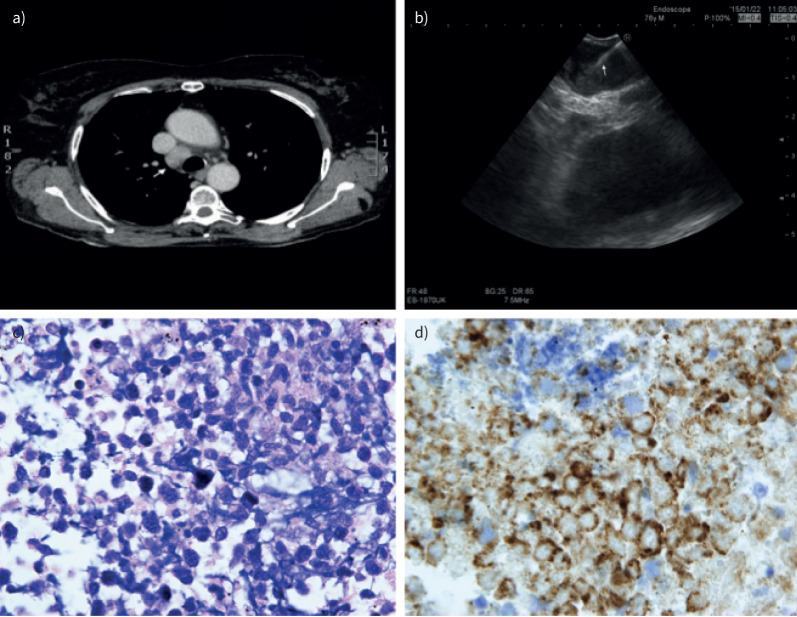

背景:支气管超声引导下经支气管针吸(EBUS-TBNA)诊断淋巴瘤的诊断准确性总体敏感性较低。缺乏细胞学针获得的组织结构降低了诊断和分型新发和复发纵隔淋巴瘤的准确性。本研究比较了EBUS-TBNA和支气管超声引导下经支气管纵隔低温活检(EBUS-TMC)对初始淋巴瘤诊断和复发病例的敏感性,分析了安全性,并评估了由于这项新技术可能避免的纵隔镜检查的数量。方法:在2023年1月至2024年1月期间,对40例同时接受EBUS-TBNA和EBUS-TMC治疗并明确诊断为淋巴瘤的患者进行了多中心回顾性观察研究。EBUS-TBNA和EBUS-TMC在同一淋巴结站进行。结果:与单独使用EBUS-TBNA和EBUS-TBNA+流式细胞术相比,EBUS-TMC的总体敏感性显著高于EBUS-TBNA (95% vs 15% vs 25%)。在新发淋巴瘤病例中,EBUS-TMC的敏感性超过EBUS-TBNA和EBUS-TBNA+流式细胞术(92%比15%比14%)。在复发病例中,EBUS-TMC的灵敏度为100%,而EBUS-TBNA和EBUS-TBNA+流式细胞术的灵敏度较低,分别为14%和41%。无并发症报道。结论:与EBUS-TBNA相比,EBUS-TMC在诊断和分型淋巴瘤方面具有更高的敏感性,无论是在疑似新发病例还是复发病例中。这项技术减少了重复手术的需要,避免了更多的侵入性和昂贵的干预,如纵隔镜检查。

Background: The diagnostic accuracy of endobronchial ultrasound-guided transbronchial needle aspiration (EBUS-TBNA) for the diagnosis of lymphoma has a low overall sensitivity. The lack of tissue architecture obtained by cytological needles decreases the diagnostic accuracy for diagnosis and subtyping of de novo and relapsed mediastinal lymphomas. This study compares the sensitivity of EBUS-TBNA and endobronchial ultrasound-guided transbronchial mediastinal cryobiopsy (EBUS-TMC) for both initial lymphoma diagnosis and recurrent cases, analyses safety, and evaluates the number of mediastinoscopies that could potentially be avoided due to this novel technique.

Methods: A multicentre retrospective observational study conducted on 40 patients who underwent both EBUS-TBNA and EBUS-TMC in the same procedure in which a definitive diagnosis of lymphoma was obtained from January 2023 to January 2024. EBUS-TBNA and EBUS-TMC were performed in the same lymph node station.

Results: The overall sensitivity of EBUS-TMC was significantly higher compared to EBUS-TBNA alone and EBUS-TBNA+flow cytometry (95% versus 15% versus 25%). In new lymphoma cases, the sensitivity of EBUS-TMC surpassed that of EBUS-TBNA and EBUS-TBNA+flow cytometry (92% versus 15% versus 14%). In recurrent cases, EBUS-TMC showed a sensitivity of 100%, while EBUS-TBNA and EBUS-TBNA+flow cytometry had lower yields of 14% and 41%, respectively. No complications were reported.

Conclusions: EBUS-TMC demonstrates superior sensitivity compared to EBUS-TBNA in diagnosing and subtyping lymphoma, both in suspected new cases and recurrences. This technique reduces the need for procedural repetitions and avoids more invasive and costly interventions such as mediastinoscopy.